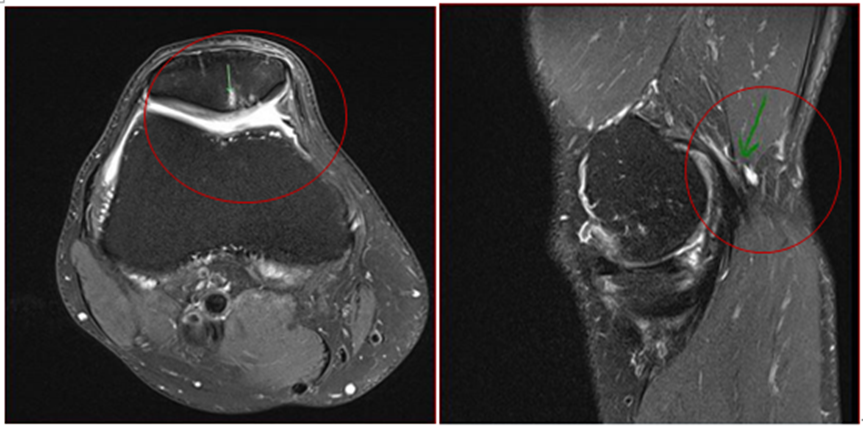

治疗九个月后,患者的临床症状仍保持稳定,核磁共振成像显示半月板撕裂情况没有进一步发展,滑膜炎显著减少和腘窝囊肿消退,但BME和SBC仍然很明显(如图2a和2b)。

图2a:间充质干细胞治疗后9个月,髌骨骨髓水肿和囊肿稳定;2b:腘窝囊肿几乎消失,图片来源:【1】